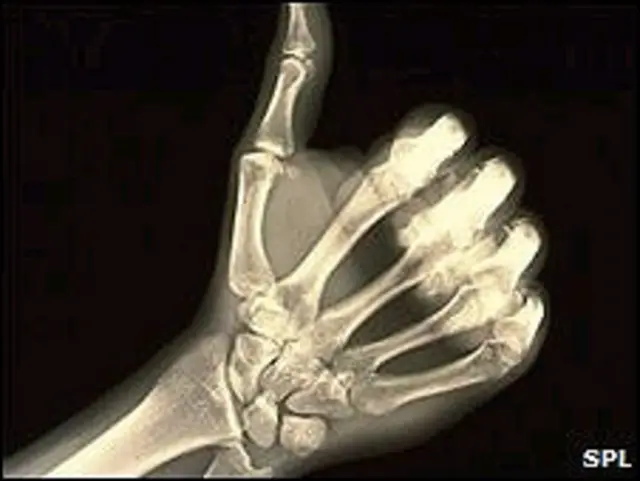

एक्स-रे के आविष्कार ने पहली बार किसी के शरीर को बिना काटे और खोले भीतर देखने की सुविधा प्रदान की जो चिकित्सा के क्षेत्र में एक बहुत ही महत्वपूर्ण क़दम था.

उन्होने कहा कि एक्स-रे मशीन ने चिकित्सा के क्षेत्र में एक क्रांति पैदा की और अब ये तकनोलॉजी इतनी विकसित हो चुकी है कि अब हम ‘पारदर्शी रोगी’ के युग में पहुंच रहे हैं.